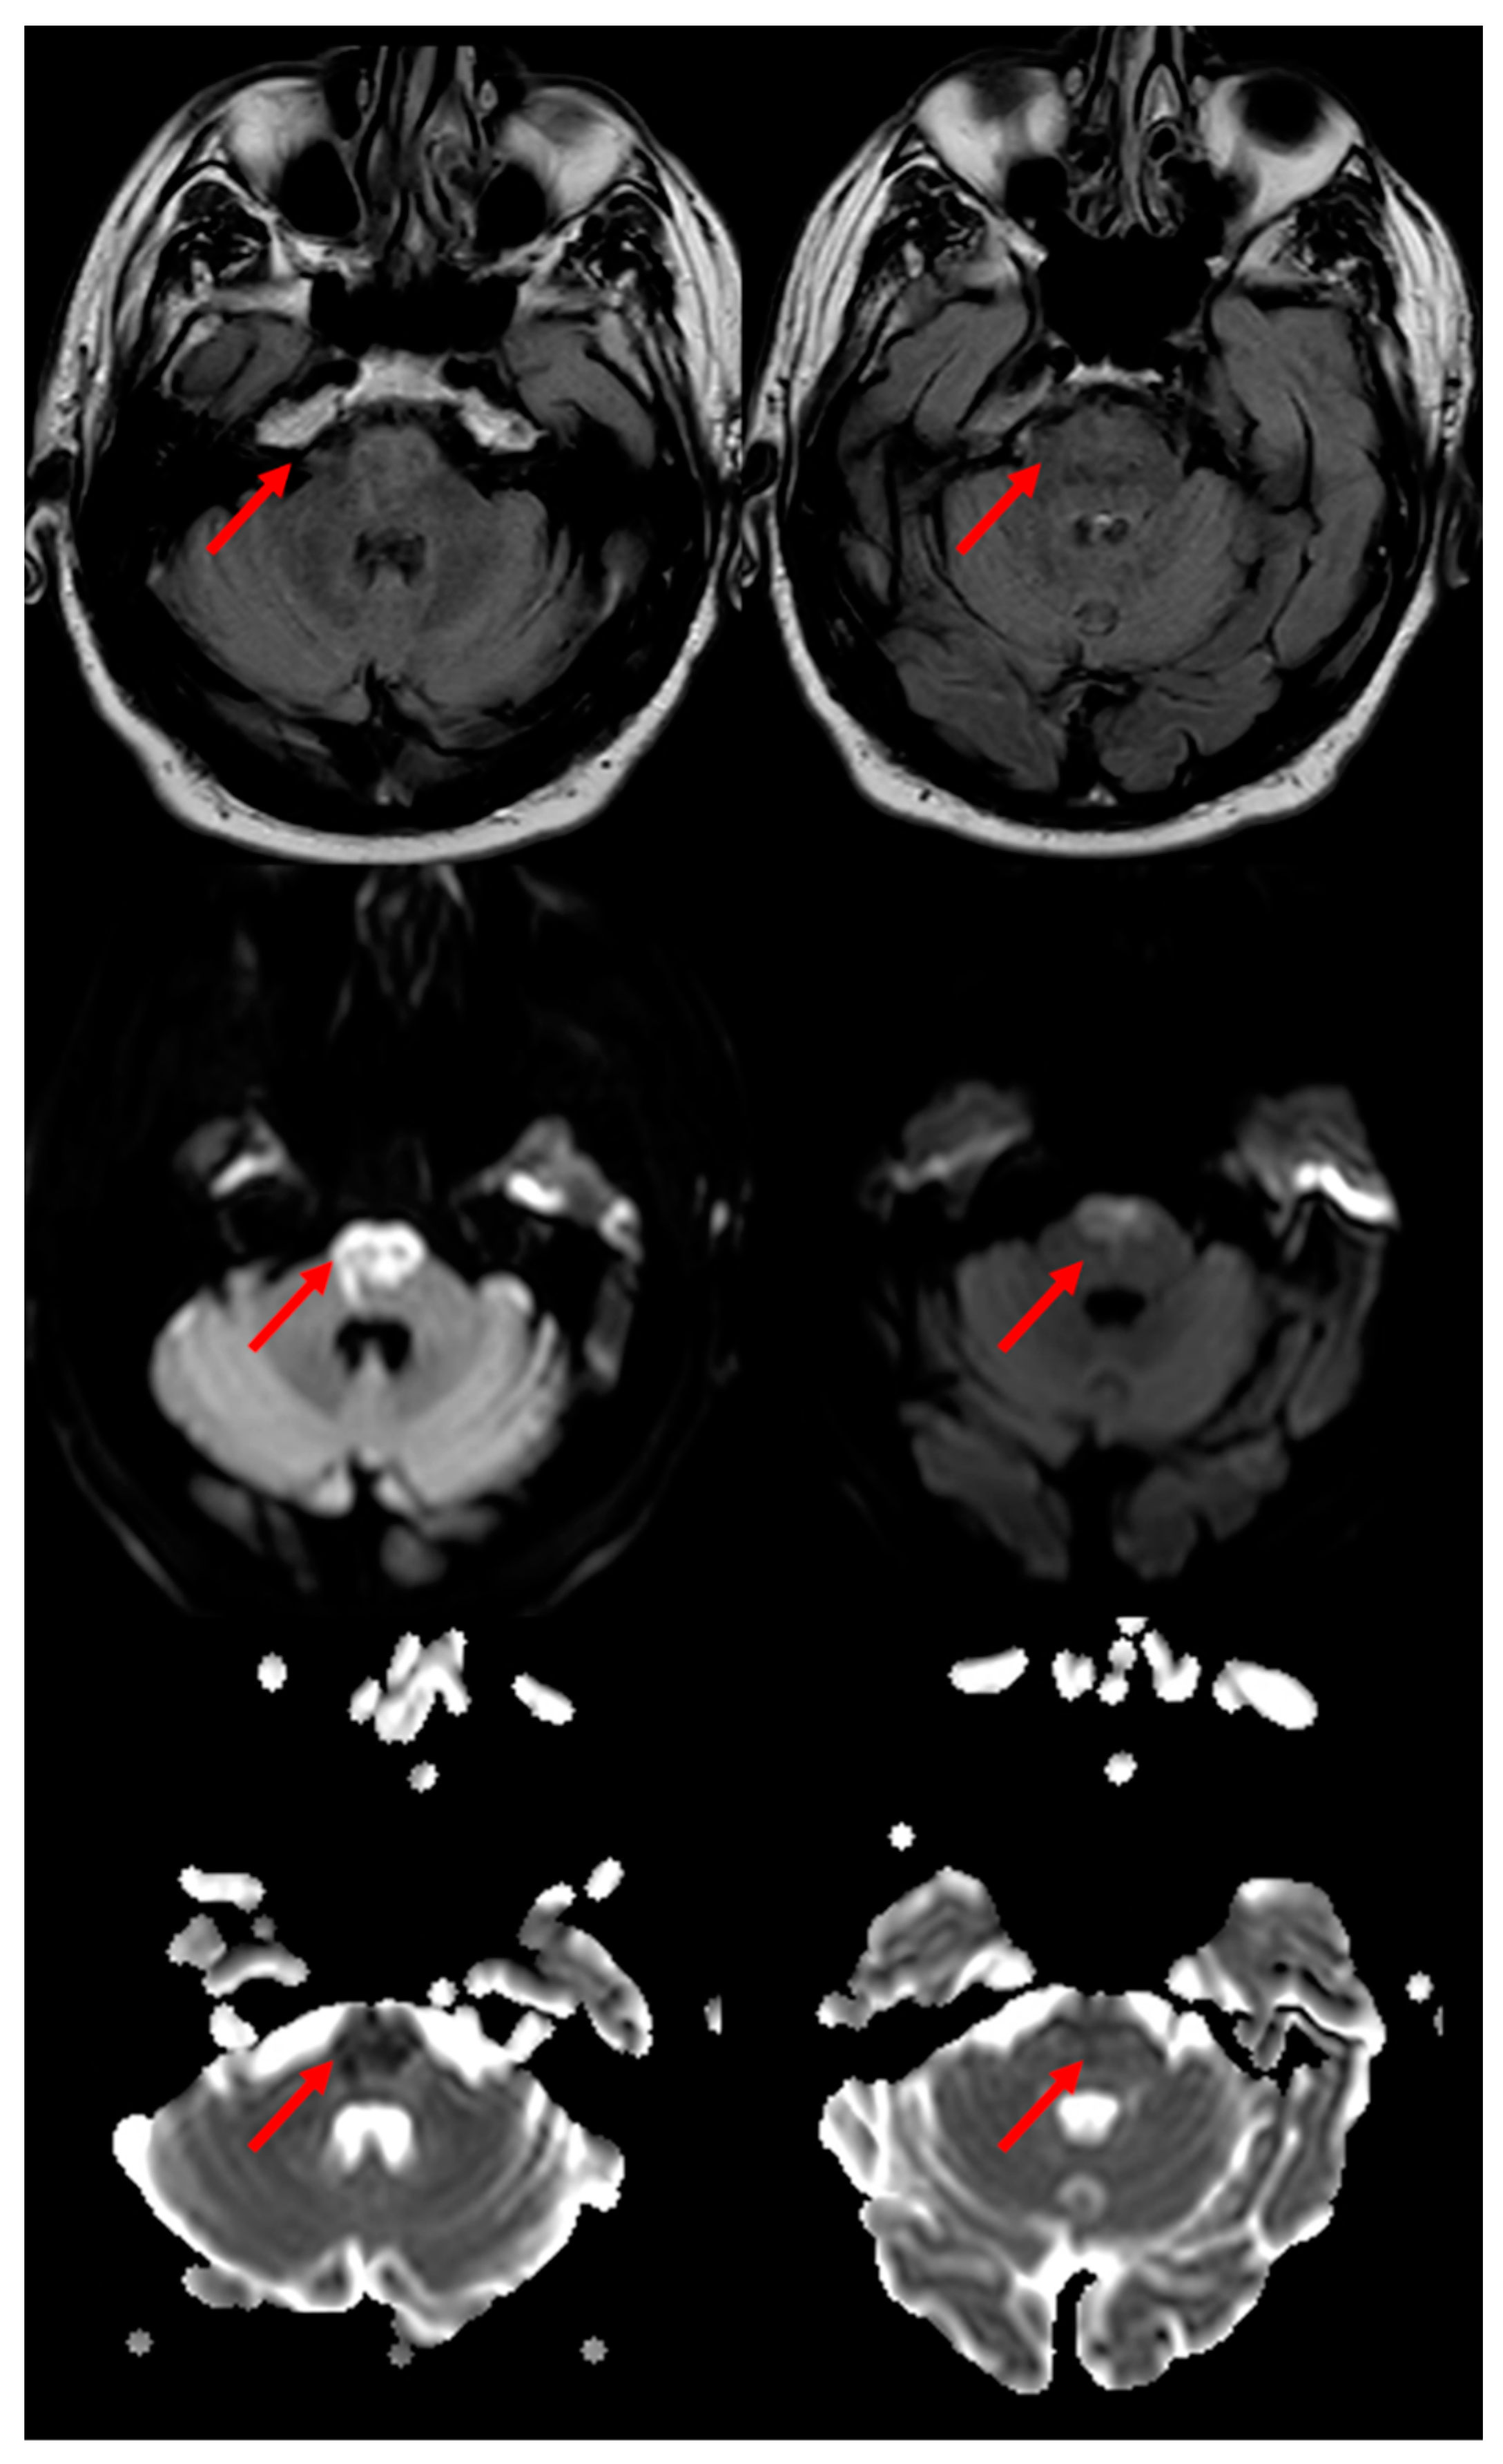

3.1. Medullary Infarction

3.2. Pontine Infarction